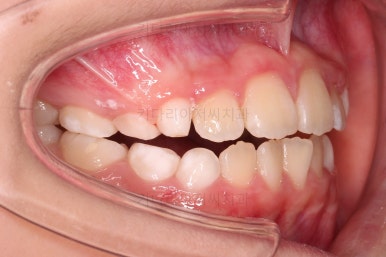

부산초등학생교정 전후 비교를 해보겠습니다.

부산초등학생교정 전후 모습을 보면 말 그대로 드라마틱한 변화네요.

특히 웃을 때 아랫니가 툭 튀어나와서 아랫니 위주로 보이던 미소가 완벽히 개선되어서 웃는 모습이 참 예뻐졌어요.

보호자분이 원하던 주걱턱도 개선되었고 초등학생 어린이 본인이 원하던 앞니 가지런함도 매우 좋아졌어요.

골든타임을 놓치지 않고 적절한 교정방법으로 좋은 협조도를 가지고 치료하니 매우 좋은 치료가 되었어요.